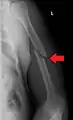

A transverse fracture of the humerus shaft